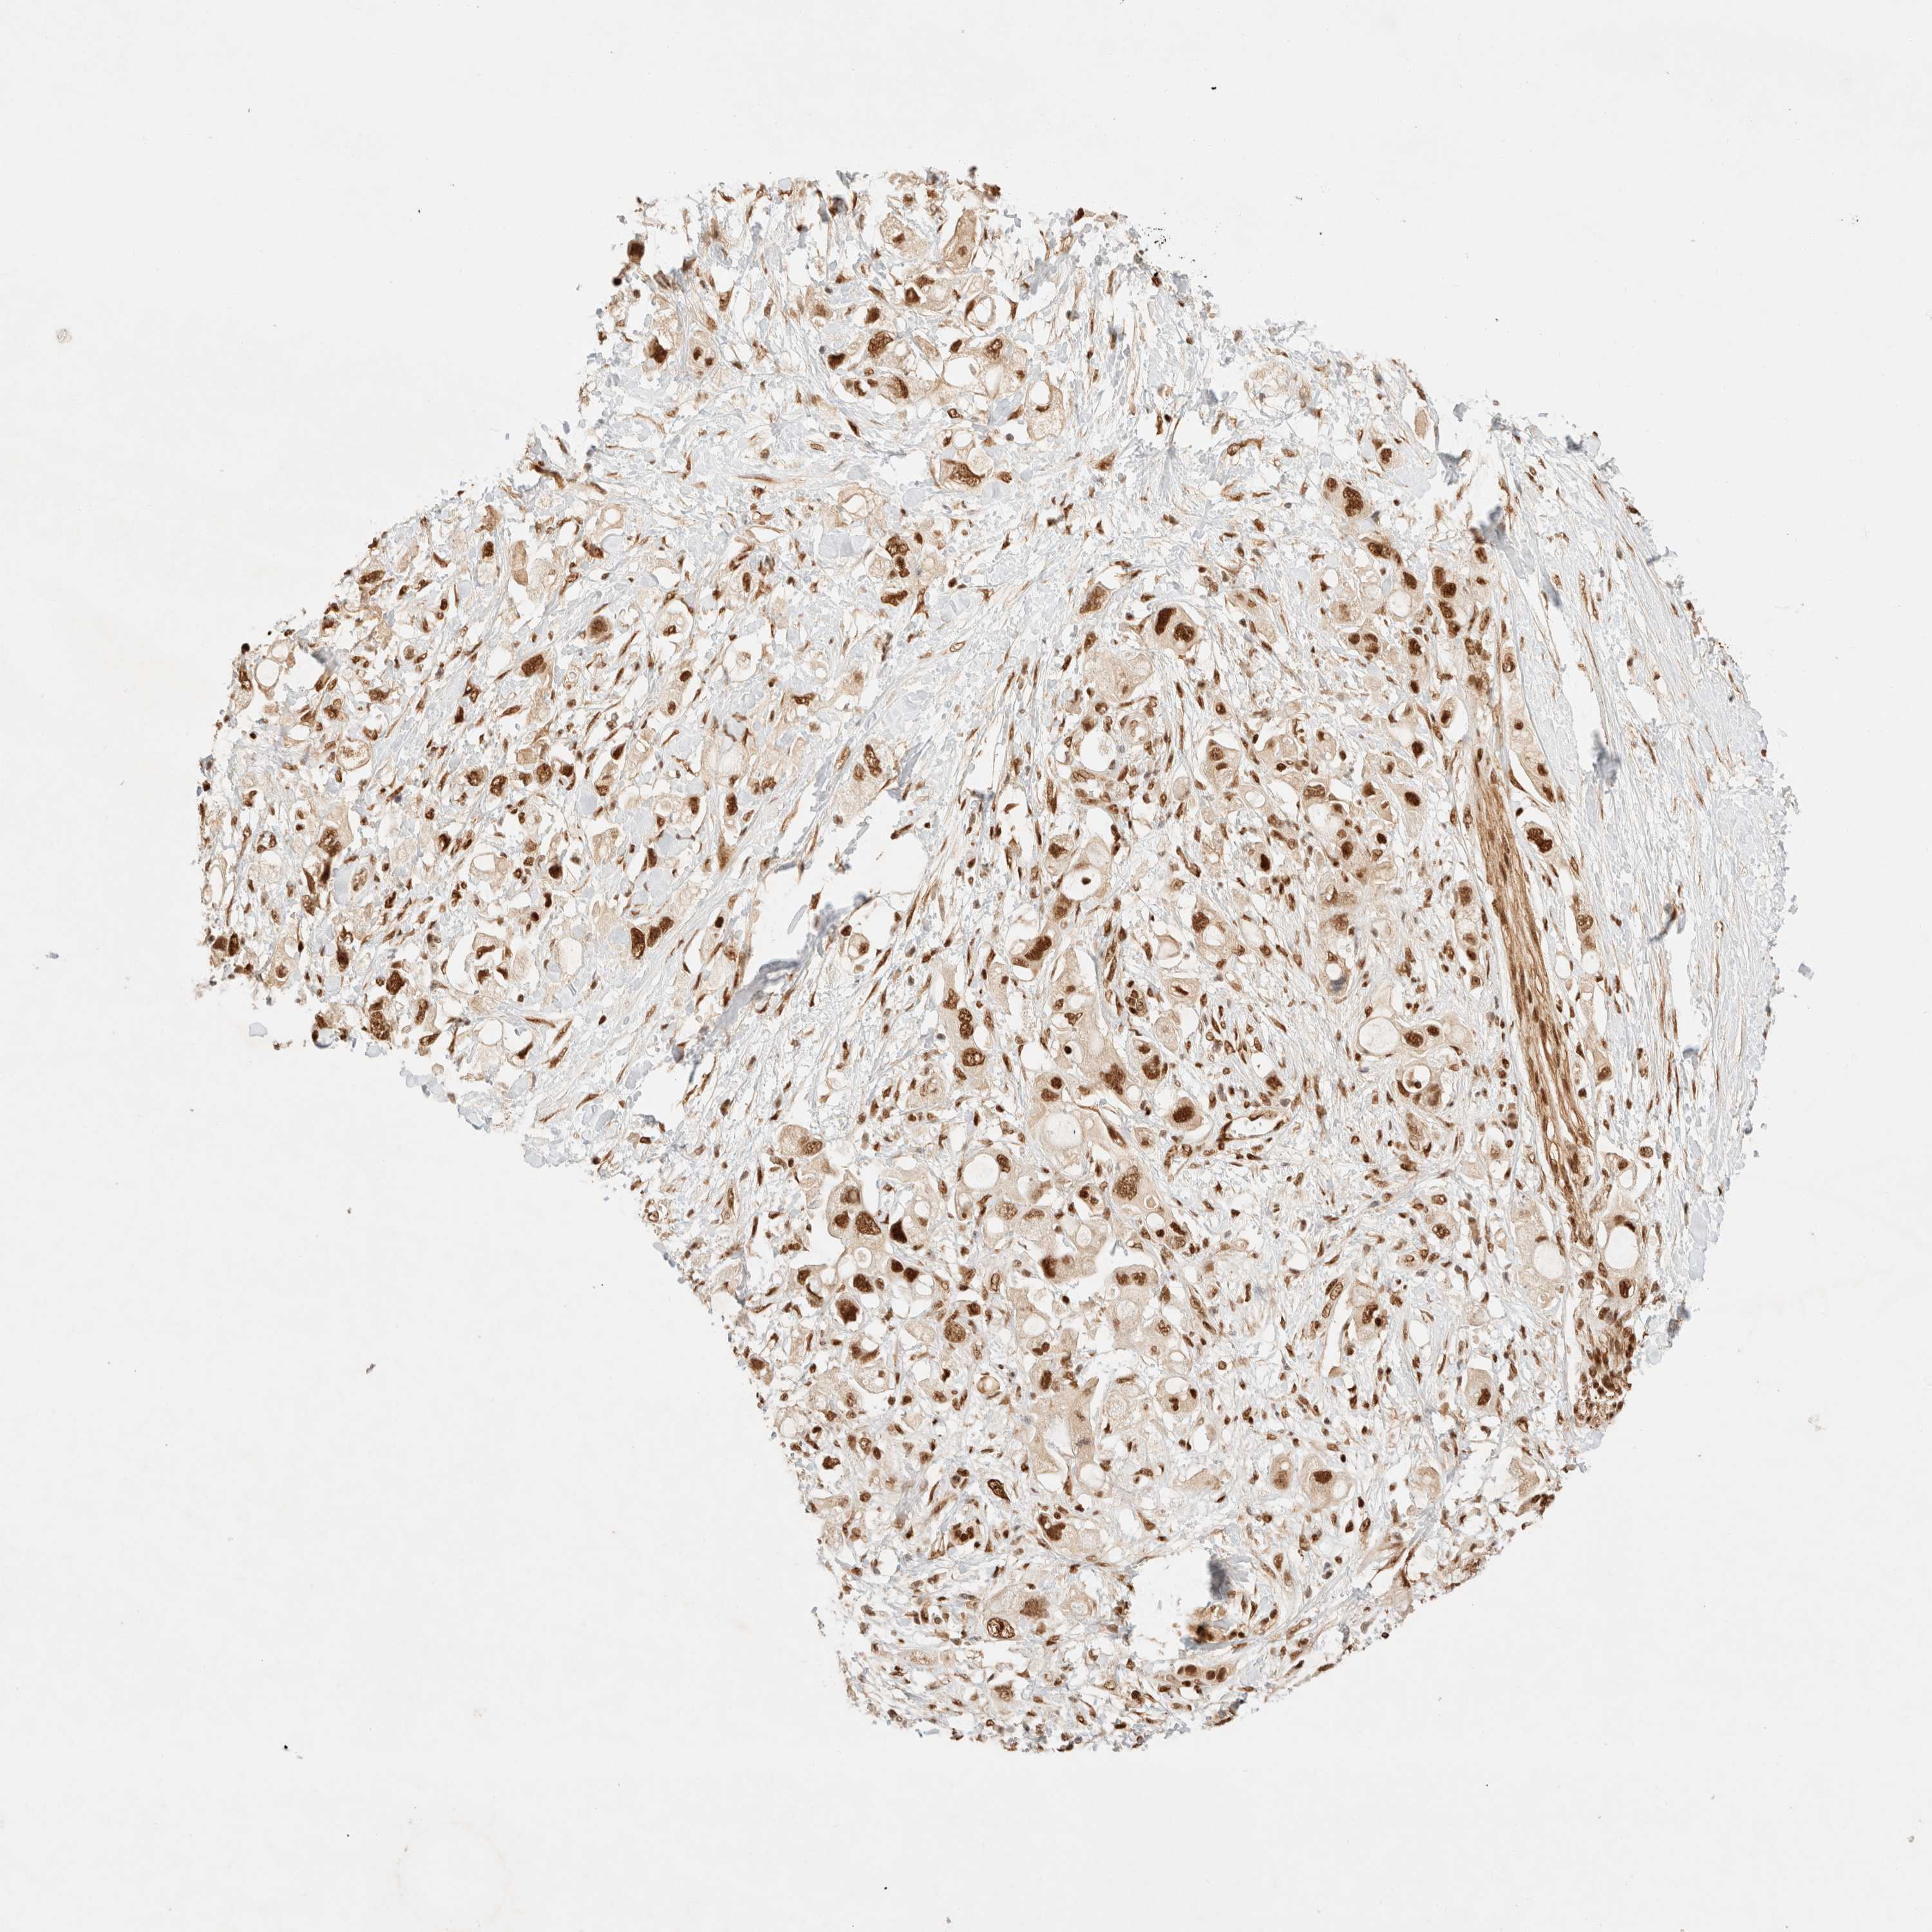

PANCREATIC CANCER - Protein expressioni

A mouse-over function shows sample information and annotation data. Click on an image to view it in a full screen mode. Samples can be filtered based on level of antibody staining by selecting one or several of the following categories: high, medium, low and not detected. The assay and annotation is described here.

Note that samples used for immunohistochemistry by the Human Protein Atlas do not correspond to samples in the TCGA dataset.

Antibody stainingi

Antibody staining in the annotated cell types in the current human tissue is reported as not detected, low, medium, or high, based on conventional immunohistochemistry profiling in selected tissues. This score is based on the combination of the staining intensity and fraction of stained cells.

Each image is clickable and will lead to virtual microscopy that enables deeper exploration of all samples and also displays staining intensity scores, fraction scores and subcellular localization as well as patient and tissue information for each sample.

Antibody HPA024630

Staining

High

Medium

Low

Not detected

Intensity

Strong

Moderate

Weak

Negative

Quantity

>75%

75%-25%

<25%

None

Location

Nuclear

Cytoplasmic/membranous

Cytoplasmic/membranous,nuclear

Adenocarcinoma, NOS